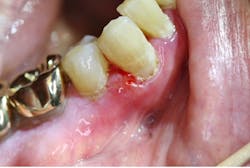

Aspirin burn

Pain is one of the main symptoms patients present with to dental offices. Aspirin burn (figure 6), or acetylsalicylic acid burn trauma of the gingiva and oral mucosa, present secondarily to patient self-medication with over-the-counter pain relief medicines. Analgesics can cause chemical burns when taken incorrectly and placed directly on the gingiva. These wounds present as irregularly shaped white lesions and can have ulcerative-type lesions at the base. Treatment includes discontinuing use of the causative agent and palliative measures.6